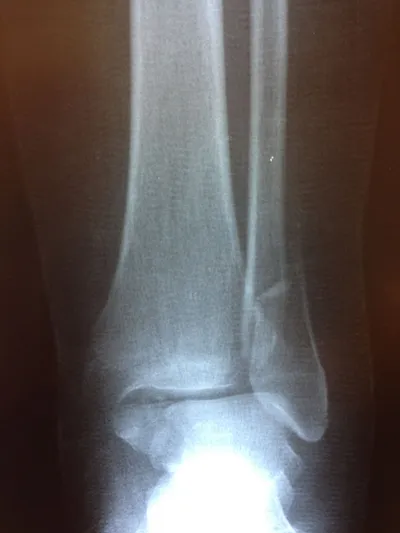

X-ray of Non Displaced Posterior Malleolar Fracture

Preop and Postop ORIF Posterior Malleolus Fracture with associated Fibular fracture

Preop and Postop Trimalleolar Fracture with Fixation of Posterior Malleolus Fracture

Preop